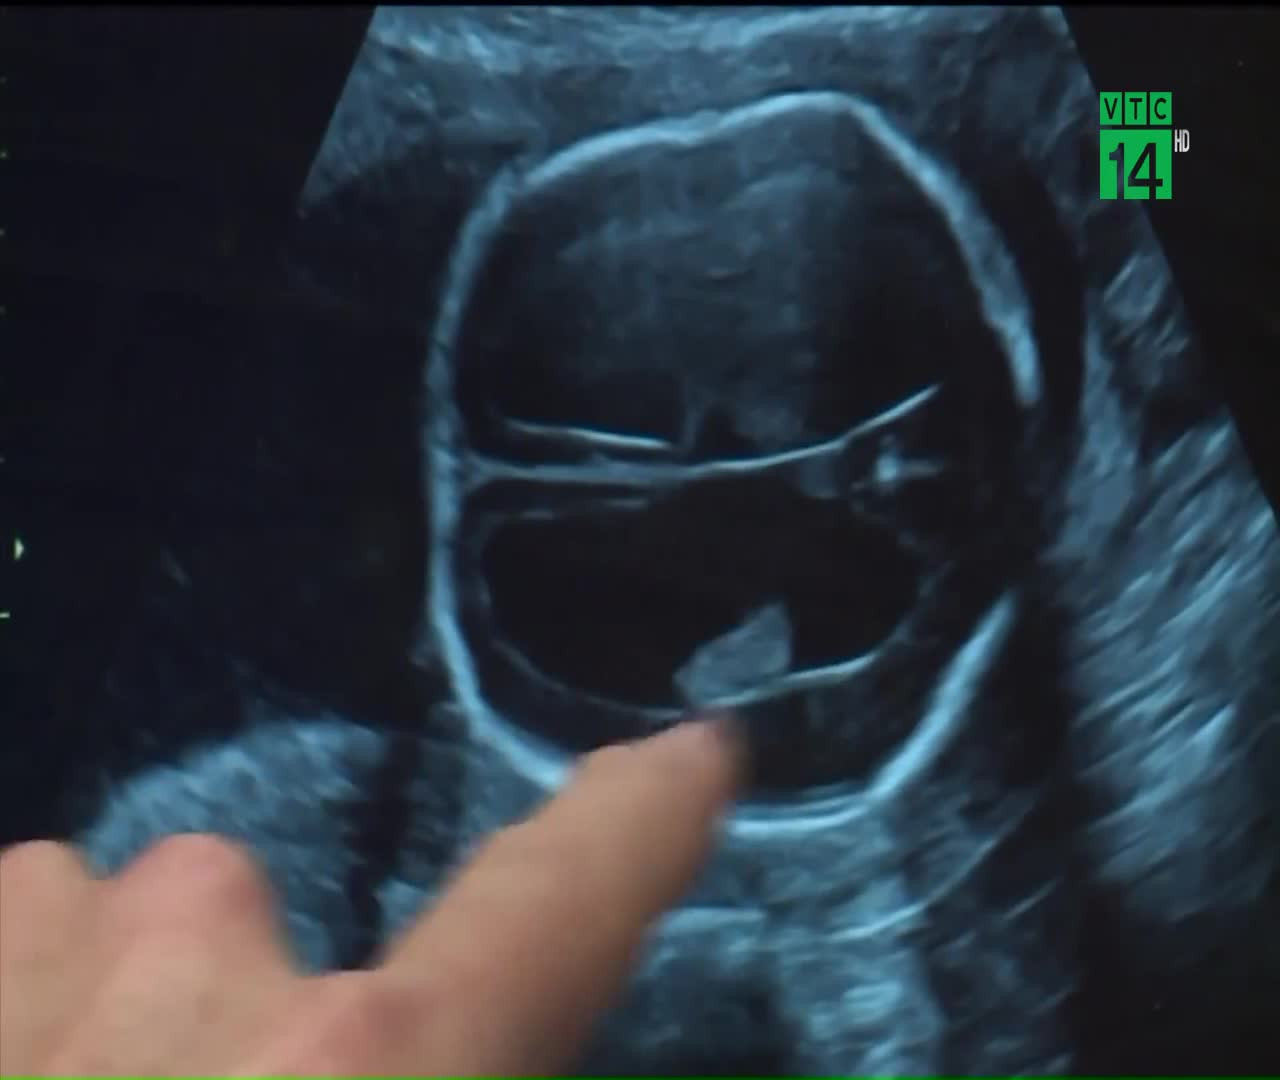

Đưa một thai nhi 19 tuần tuổi ra khỏi bụng mẹ, tiến hành làm phẫu thuật và sau đó đưa bé trở lại bụng mẹ, có lẽ nhiều người đang nghĩ, đây là một câu chuyện hoang tưởng, chỉ xuất hiện trên phim ảnh.

Đưa thai nhi 19 tuần tuổi ra ngoài phẫu thuật rồi trả lại bụng mẹ